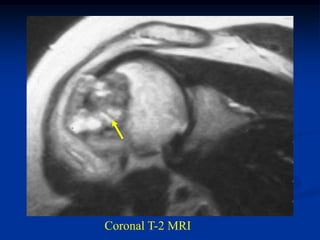

Coronal T-2 MRI

Case #554

42 year female

enchondroma        tumor

proximal humerus